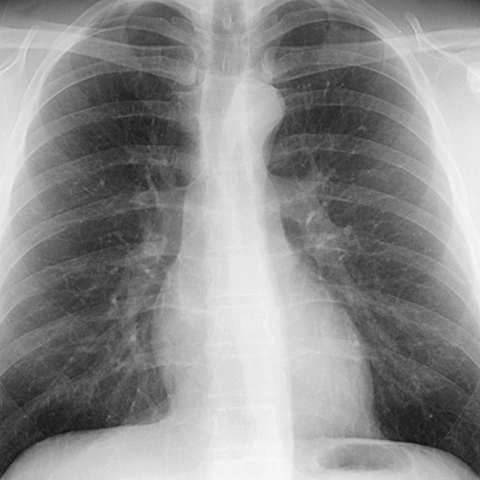

Normal anatomy of the aorta (CXR) [1 of 5]